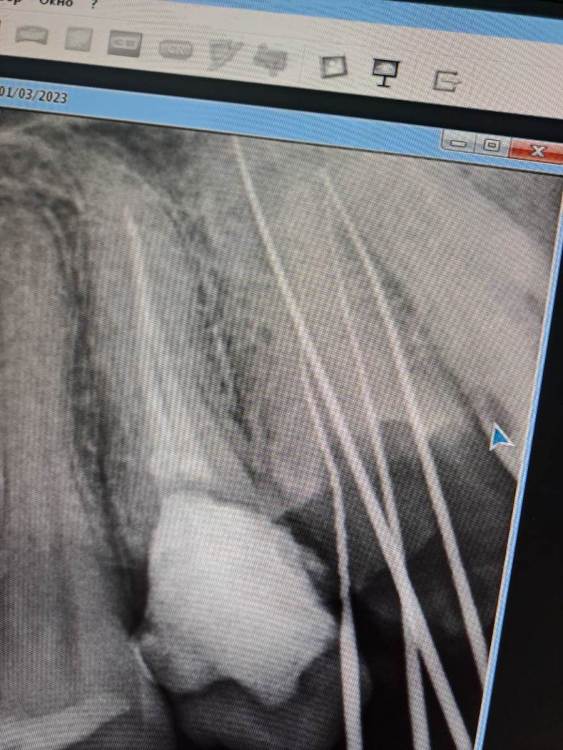

FISSMAN Опубликовано 4 марта, 2023 Поделиться Опубликовано 4 марта, 2023 (изменено) Качественно ли пролеченны зубки и каналы ? Фото есть Изменено 4 марта, 2023 пользователем FISSMAN Ссылка на комментарий

FISSMAN Опубликовано 7 апреля, 2023 Автор Поделиться Опубликовано 7 апреля, 2023 24.03.2023 в 09:20, IvanK сказал: Здравствуйте Если Вы не доверяете своему врачу, то нужно найти врача, которому Вы сможете доверять для ответов на Ваши вопросы нужно больше объективных данных (еще снимки, фото) Доверяю после лечения мне становится легче, хотел узнать про качество. Вот фото после лечения этих зубок Ссылка на комментарий

IvanK Опубликовано 8 апреля, 2023 Поделиться Опубликовано 8 апреля, 2023 выглядит все не плохо для более достоверной оценки нужна компьютерная томография 1 Ссылка на комментарий